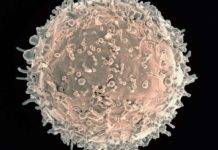

Anteriormente, los científicos en Alemania descubrieron que la transmisión del VIH está relacionada con la presencia de un amiloide fibrilar en el semen. Este fibrilar – una pequeña estructura, con carga positiva derivada de una proteína más grande – promueve la infección por VIH, ayudando a los virus encuentran y se unen a su objetivo: T CD4 células blancas de la sangre. En la edición de mañana de Cell Host & Microbe, los investigadores en el laboratorio de Warner C. Greene, MD, PhD, director de investigación de virología y la inmunología en Gladstone, describe un segundo tipo de fibrillas, que también tiene esta capacidad.

La transmisión sexual es para la inmensa mayoría de las infecciones por el VIH, y el semen es el modo de clave del virus de transporte. Estudios anteriores realizados por los Dres. Roan y Greene revela el mecanismo por el cual una carga positiva fibrilar en el semen – llamada SEVI – atrae el VIH como un imán, la unión a la carga negativa del VIH y ayudar a infectar a las células T CD4. En este caso, se dedicaron a investigar si los otros componentes del semen también jugó un papel.

En experimentos de laboratorio sobre muestras de semen humano, se identificó un segundo grupo de fibrillas -derivados de las grandes proteínas llamadas semenogelins – que mejoran la infección por el VIH así como SEVIhace. La eliminación de estos y otros componentes de carga positiva del semen disminuye la capacidad del VIHpara infectar las células T CD4 de sangre blancas. Lo que confirma el papel de estas fibrillas en la promoción dela infección por